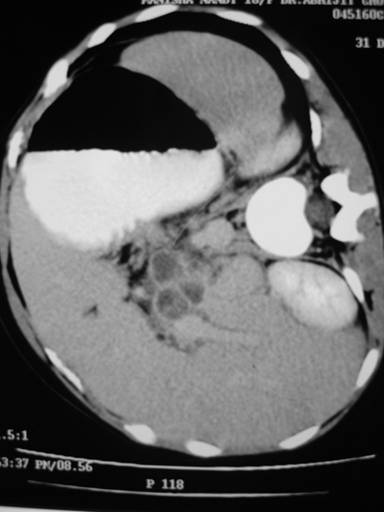

A 13-year-old girl presented with dull aching upper abdominal pain unrelated to meals and non-radiating type for the past 3 months. Other symptoms were anorexia, 4.5 kg weight loss, and weakness. The patient did not have fever, jaundice or gastrointestinal bleeding. Physical examination revealed pallor, enlarged left supraclavicular lymph node, and deep seated tenderness in the epigastrium. Investigations revealed hemoglobin of 9.4 g/dL (reference range: 12-15 g/dL), total leukocyte count of 7,600 mL-1 (reference range: 4,000-11,000/mL-1) with a normal differential count, erythrocyte sedimentation rate of 46 mm/first hour (reference range: 5-15mm/first hour). Results of HIV serology were negative, and chest radiograph was normal. CECT abdomen showed enlarged pancreatic head with multiple enlarged peripancreatic lymph nodes. These lymph nodes showed central necrosis with peripheral rim enhancement (Figure 5). FNA from left supraclavicular lymph node showed nonspecific infection. EUS-guided FNA (using Echotip 22G, Wilson Cook needle, Salem, NY, USA) from the mass showed epithelioid cell granuloma and caseation necrosis. She received antituberculous drugs for 6 months. Patient was well at 24-month follow-up.

Figure 5. CECT abdomen showing peripancreatic lymph nodes with central necrosis and peripheral rim enhancement (Case #3). |